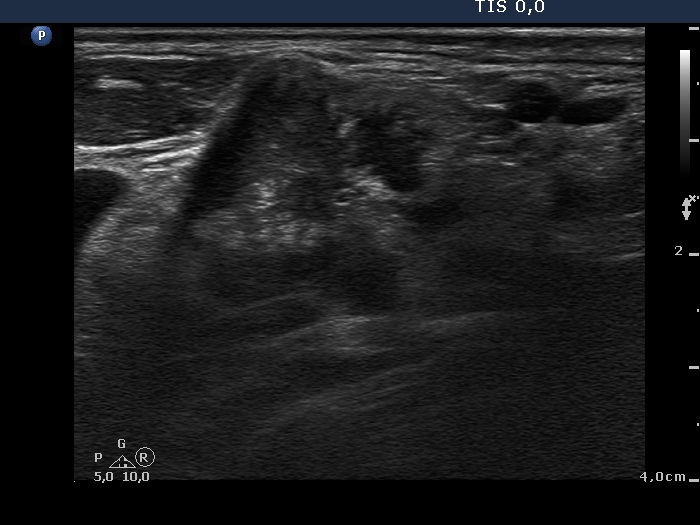

Ultrasonography: The thyroid was intact. There were multiple nodes in both supraclavicular regions. The nodes presented an absolutely irregular shape and border. They contained numerous hyperechogenic circumscribed areas.